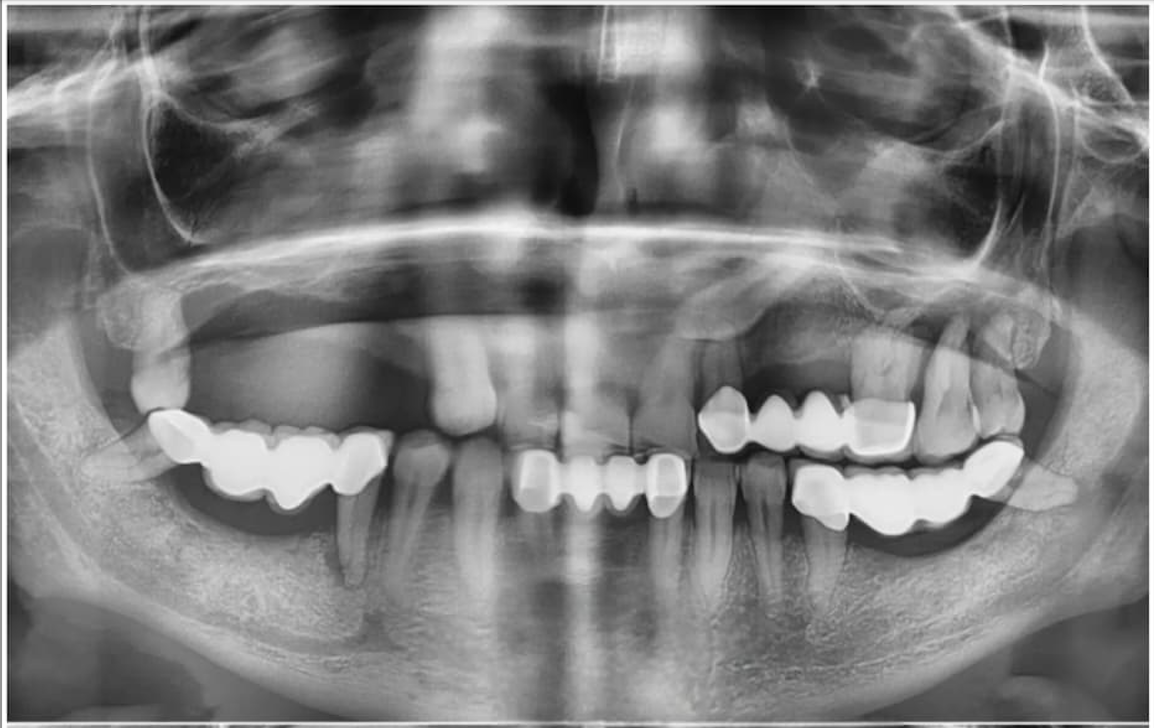

Before

Before treatment

After

After treatment

Full Arch Restoration